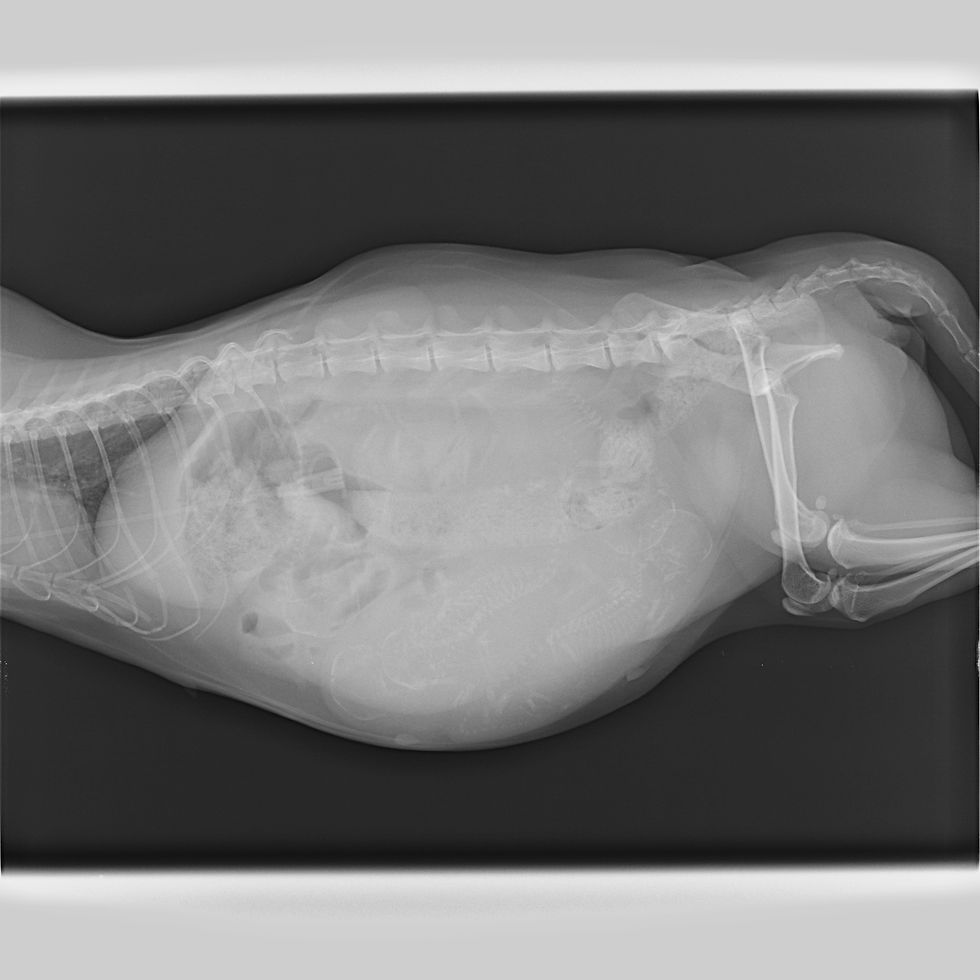

レントゲンを撮ってみると5頭赤ちゃん猫がいました。

超音波でおなかの中の赤ちゃんねこを見てみると、心臓が止まっている子もいるのです。心臓が動いている子も心臓の動きが鈍くなっている子もいたのです。なにかがおかしいのです。。。

お母さんねこちゃんは血液検査で重度の貧血があり、手術も怖かったのですが、お母さんねこちゃんの元気がない原因が妊娠していることにありそうだったので、緊急で帝王切開を行いました。

おなかをあけて気づいたのですが、どうも子宮が捻じれていたのです。結果、子宮に向かう血管も捻じれてあかちゃんねこに向かう血液も滞っていた様子でした。

あかちゃんねこを急いで取り出して、看護師さんたちに蘇生をしてもらったのですが、5頭とも残念ながら助かりませんでした。

お母さんねこちゃんは子宮が捻転し、卵巣と子宮の一部が血行不良で変色していたため、卵巣子宮を摘出を取らざるを得ない状態でした。